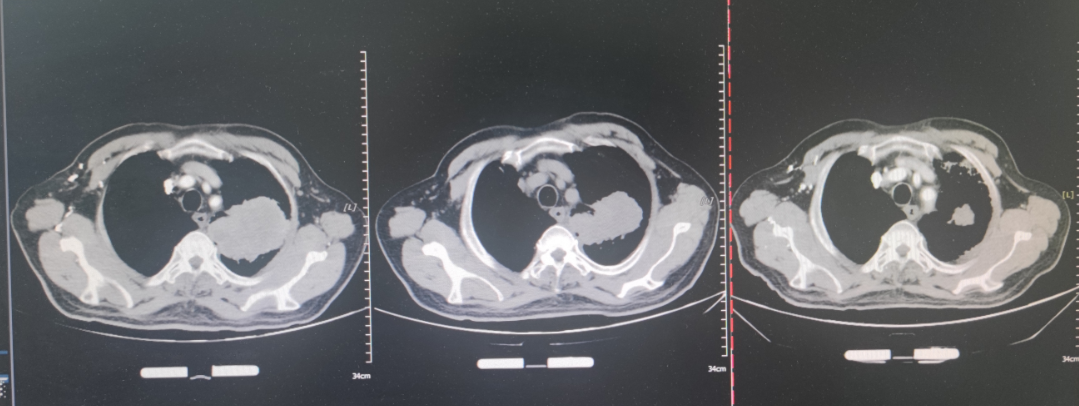

现病史:2024-03-05,患者因“发现左肺上叶占位3月余”就诊于外院,完善胸部增强CT提示:左肺上叶软组织肿物,考虑肺癌;两肺多发微小实性结节,不除外转移;右肺下叶磨玻璃结节,考虑腺体前驱病变可能。

影像学检查:2024-03-05 胸部增强CT:左肺上叶软组织肿物,考虑肺癌;两肺多发微小实性结节,不除外转移;右肺下叶磨玻璃结节,考虑腺体前驱病变可能;肺气肿;两肺多发肺大泡;右肺中叶及左叶少许条索影;主动面及冠状动脉钙化;右侧第6肋骨密度不均,肝内多发低密度,考虑囊肿;双侧肾上腺增粗。

放疗:2025-5-23起,行Lattice放疗,95%GTV vertex1-6:32Gy/8Gy/4f,95%PTV 50Gy/2Gy/25f,期间给予抗肿瘤、升血、促进食欲、补液,并使用放疗增敏剂甘氨双唑钠增敏。放疗后患者饮食及食欲改善,乏力较前好转。

疗效评估:2025-8-30复查,对比前片,左肺Ca治疗后所见;双侧肾上腺占位,考虑转移;双肺多发小结节,较前相仿;左肺炎性病变;双肺气肿。